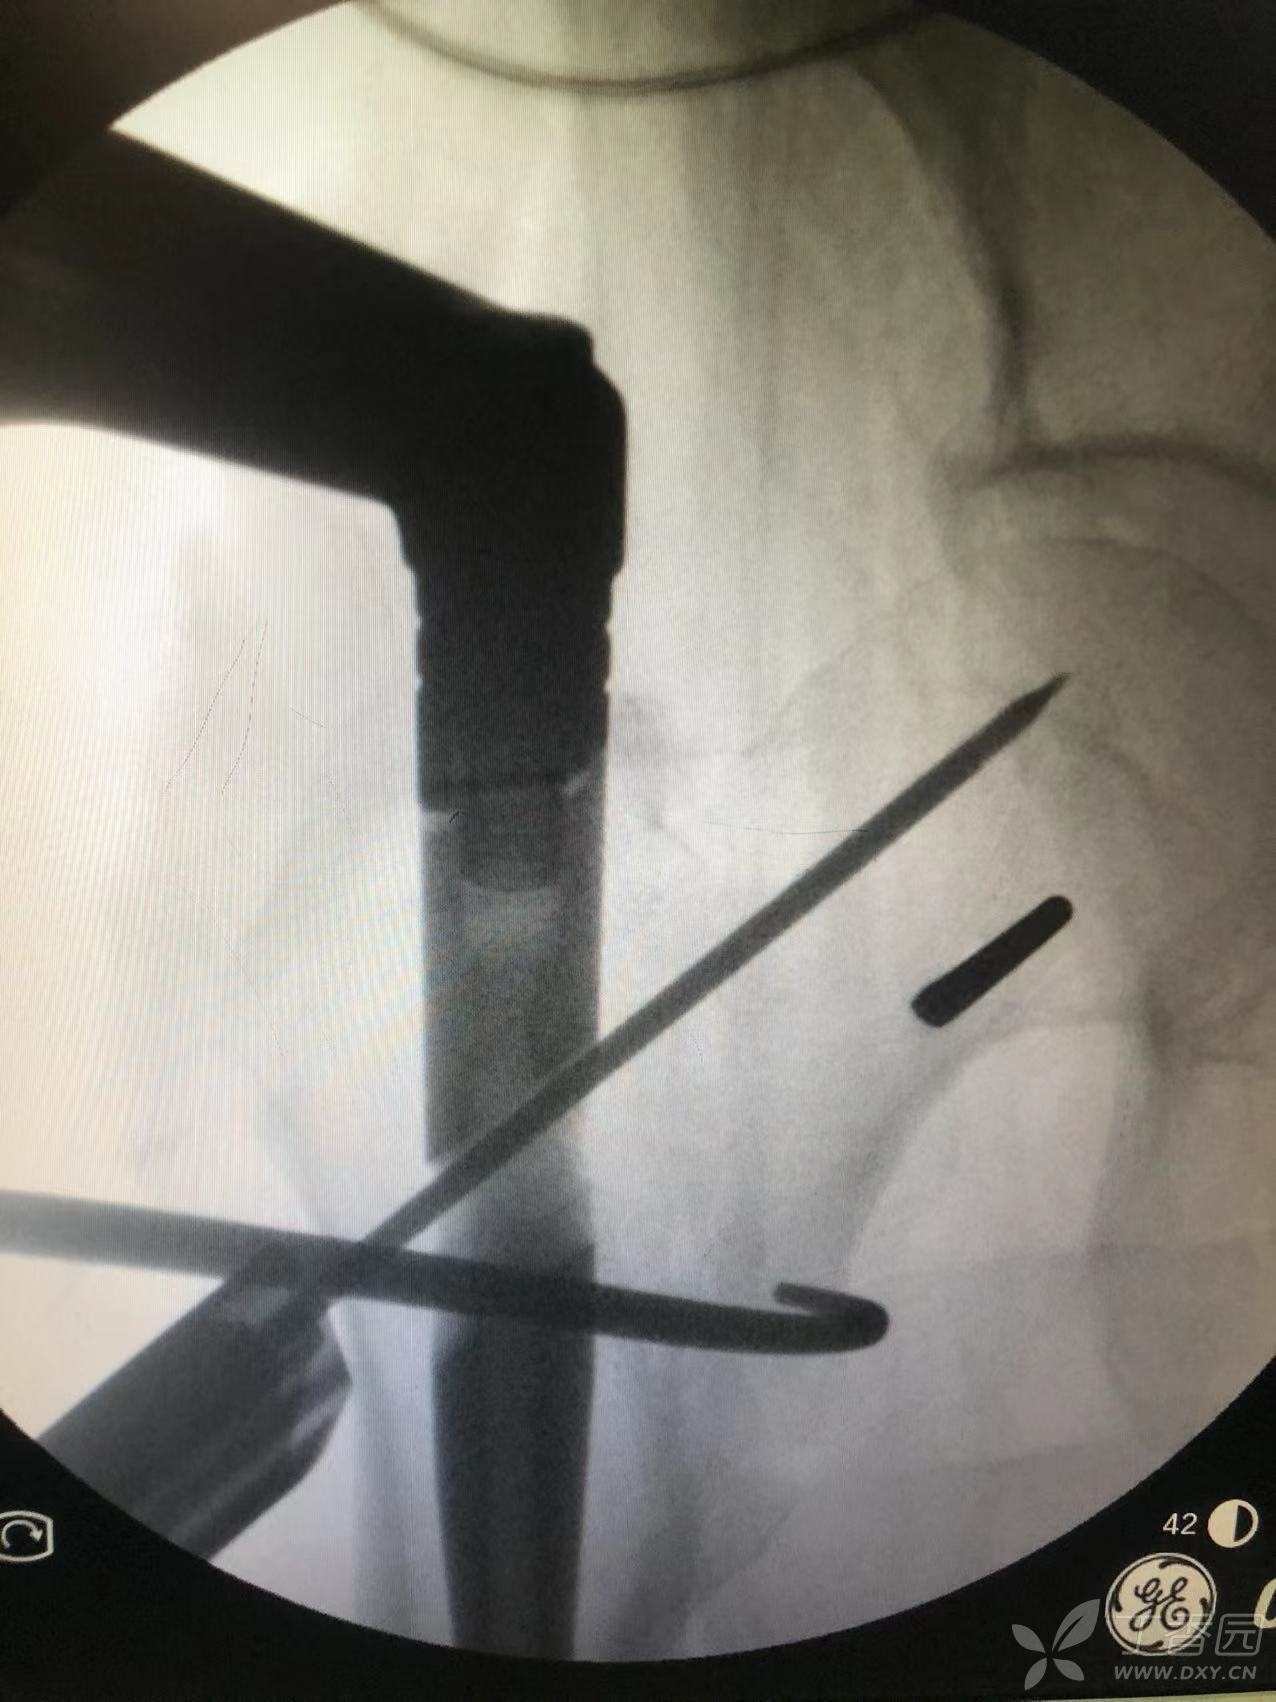

通过骨勾经头钉口经股骨前侧钩住小转子,见复位良好后打入主钉导针。

扩髓后插入主钉,调好前倾角后打入头钉导针。

依次打入头钉及拉力钉并加压固定。

打入远端锁钉。